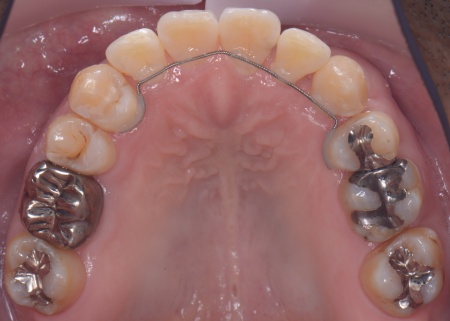

①抜歯をしてから歯並びを整える「抜歯矯正」 今回のケースでは、左上下の奥歯各1本(第3大臼歯)、右下の奥歯1本(第3大臼歯)、左上下と右下の奥歯各1本(第1小臼歯)の計6本の抜歯が必要です。 また、奥歯の噛み合わせは正常だったことから、それを維持しながら歯並びを整えるために以下の方法を採用します。 ②矯正治療後、歯周病を発症している左下奥歯(第1大臼歯)を温存するために、失われた骨や歯茎を再生する「歯周再生療法」を行う まずは歯の移動スペースを確保するために、計6本の歯を抜きます。 矯正治療終了後、歯の後戻りを防ぐため、上下前歯の裏側にワイヤーを接着して固定させる「フィックスリテーナー」を装着しています。 その後、左下奥歯に歯周再生療法を行って歯周病が改善したことを確認し、治療を終了しました。 |